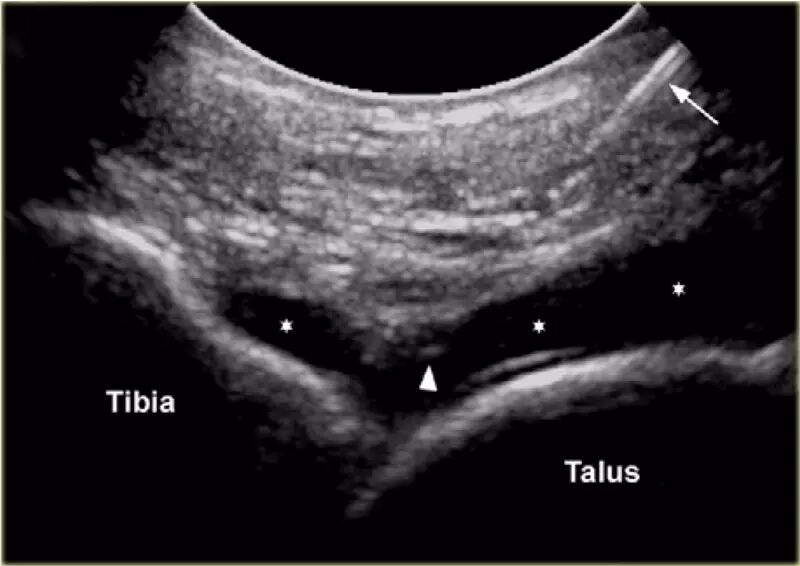

胫骨关节      CT或MR关节镜可用于查询韧带,骨软骨或软骨损伤,评价自由体或查询骨软骨病变的稳定性。对于踝关节(胫骨关节)的注射,患者仰卧,足部轻微的跖屈。用超声波检查胫骨关节的内侧,以确定合适的注射部位,同时检查任何过量的关节液。我们使用小型弯曲阵列8 MHz传感器,但如果优选,可以使用18-12 MHz线性阵列传感器。 探头的长轴保持在矢状面内。

通常为22号(长度:30mm)的针被引入与在前关节空间的内侧上的换能器的长成像轴线,内侧到前胫骨韧带,避免韧带和血管。应该确定距骨穹顶和悬垂的前胫骨唇。 针头在胫骨远端成角度地进入远侧胫骨的腹侧唇下的关节,瞄准远侧胫骨的关节表面。感觉到接触,并且再次确保针尖离开胫骨软骨并且斜面面向接头。

将8-10ml的对比剂注入胫骨关节,并且看到前囊与流体一起膨胀。

患者不应该有疼痛而抵抗。